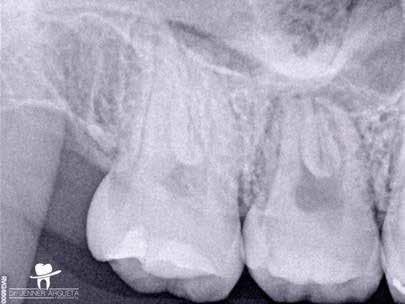

Krell és Caplan kutatásában 2086 repedt fogat vizsgáltak meg. A vizsgált fogak között leggyakrabban a második alsó nagyőrlőfogak (36%), majd ezt követően az első alsó nagyőrlők (27%), és végül az első felső nagyőrlők (18%) fordultak elő. A kutatási eredményeik szerint a fogbél állapota nem befolyásolta jelentős mértékben a kezelés várható kimenetelét. (Irreverzibilis pulpitis 85%; necrosis 80%; korábban gyökérkezelt 74%). A kimenetel szempontjából ugyanígy indifferens volt a páciensek neme, életkora, a kezelés időpontja, a fog pozíciója, a fog helyreállítása során használt anyag típusa, valamint az érintett fogfelszínek száma. 2014 júliusában egy 45 éves hölgy páciens azzal a panasszal kereste fel a rendelőnket, hogy nagyjából 10 napja egy fájdalmas duzzanat alakult ki a jobb felső első kisőrlője koronája mellett (14). A klinikai vizsgálat során egy amalgámtömést találtunk a panaszos fogban. A tömés széli zárása nem volt megfelelő, a disztális záróléc és a tömés között rést tapasztaltunk. A fog disztobukkális és linguális felszíne mellett 8 mm-es csontos tasakokat mértünk. A periapikális felvételen az 14-es foggyökér disztális felszínének megfelelően vertikális irányú radiolucens felritkulást észleltünk. A klinikai vizsgálat során a mesiális zárólécet kettéválasztó törésvonalat detektáltunk (17–18. ábra). A fogszenzibilitás vizsgálata során negatív eredményt kaptunk. A páciensnek ismertettük az elérhető terápiás lehetőségeket: 1, a 14-es fog eltávolítása, majd a foghiány 3 tagú cementezett híddal történő pótlása; 2, a 14-es fog eltávolítása, kemény- és lágyszöveti augmentáció, majd implantátum behelyezése; 3, a 14-es fog gyökérkezelése, gyökértömése és ezt követően a csücsökborítást biztosító restaurátum készítése. Arra is felhívtuk a páciens figyelmét, hogy a 3. terápiás lehetőség választása esetén nem tudjuk a fogmegtartás sikerességét garantálni, de végül – főként anyagi okok miatt – mégis ezt a terápiás opciót választotta. Fontos megjegyezni, hogy a repedt fogak ellátási lehetőségeit a törésvonal mélysége, elhelyezkedése, lefutása nagyban befolyásolja. A kezelés megtervezése során a fog és a fogat körülvevő szövetek állapotával kapcsolatos számtalan különböző faktort kell egyidejűleg figyelembe vennünk. A gyökérkezelést követően a gyökértömést meleg vertikális kondenzációs technikai alkalmazásával készítettük el (19. ábra). A hozzáférési nyílást folyékony és hibrid kompozit tömőanyag segítségével zártuk. A zárás elkészítése során a dr. David Clark által kifejlesztett Bioclear matricarendszert alkalmaztuk. A 6 éves kontroll során készített (2020) röntgenfelvételen a csontos defektus telődése volt megfigyelhető. Ez is a parodontális defektus gyógyulását igazolta (20–21. ábra).

17. ábra: A 14-es fog gyökerének disztális felszíne mellett vertikális csontpusztulásra utaló jelek észlelhetőek. Klinikailag ezen a területen 8 mm mélységű tasakmélységet mértünk. – 18. ábra: A 14-es fog disztális zárólécének megfelelően törésvonal észlelhető, ugyanakkor a csücskök teljes szeparálódására utaló jelek nem láthatóak. Az amalgámtömés eltávolítását követően jól megfigyelhető volt a törésvonal teljes lefutása. – 19. ábra: A gyökértömés elkészítése során meleg vertikális kondenzációs technikát alkalmaztunk. A felvételeken oldalcsatornák jelenlétére utaló jelek is észlelhetőek. – 20–21. ábra: A 2020-ban készült kontrollfelvételeken jól látható a csontos defektus telődése. A radiológiai jelek alapján (jól lekövethető gyökérhártyarés) a parodontális ligamentumok regenerációját is vélelmezzük.